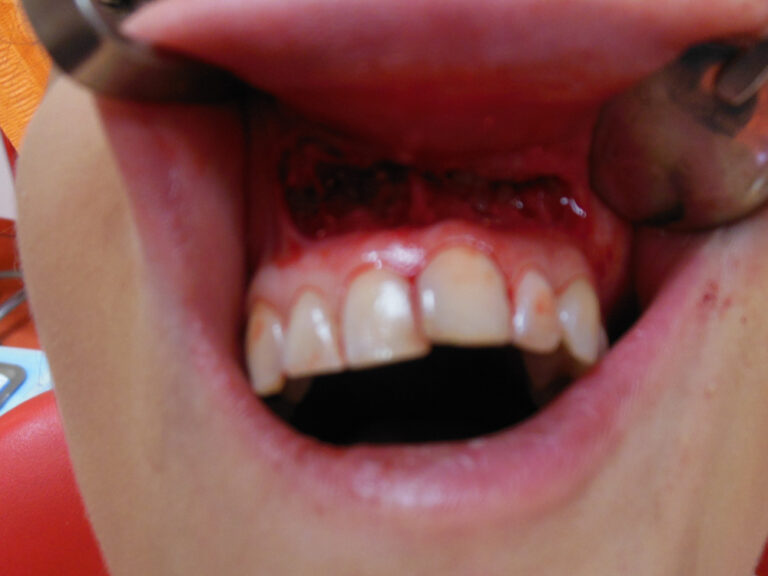

Implanty zygomatyczne

Przykłady implantologii